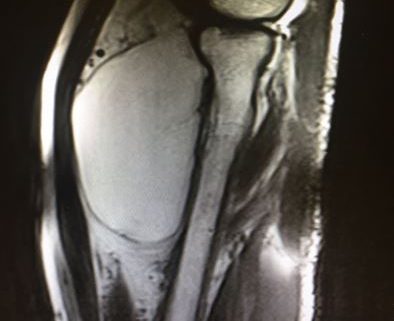

Resonancia Magnética diagnóstica que evidencia lipoma

Os presento un ejemplo/caso de un paciente que sigo en la consulta tras acudir por un bulto en el antebrazo derecho, de muchos años de evolución. A pesar de ser prominente el paciente no tenía ningún síntoma, ni el más mínimo, ni dolor, ni pérdida de movilidad, ni de tampoco de fuerza. Las pruebas diagnósticas confirmaban que se trataba de un lipoma claramente. Tras explicarle lo que os he expuesto, el paciente decidió no operarse y vamos haciendo el correspondiente seguimiento.